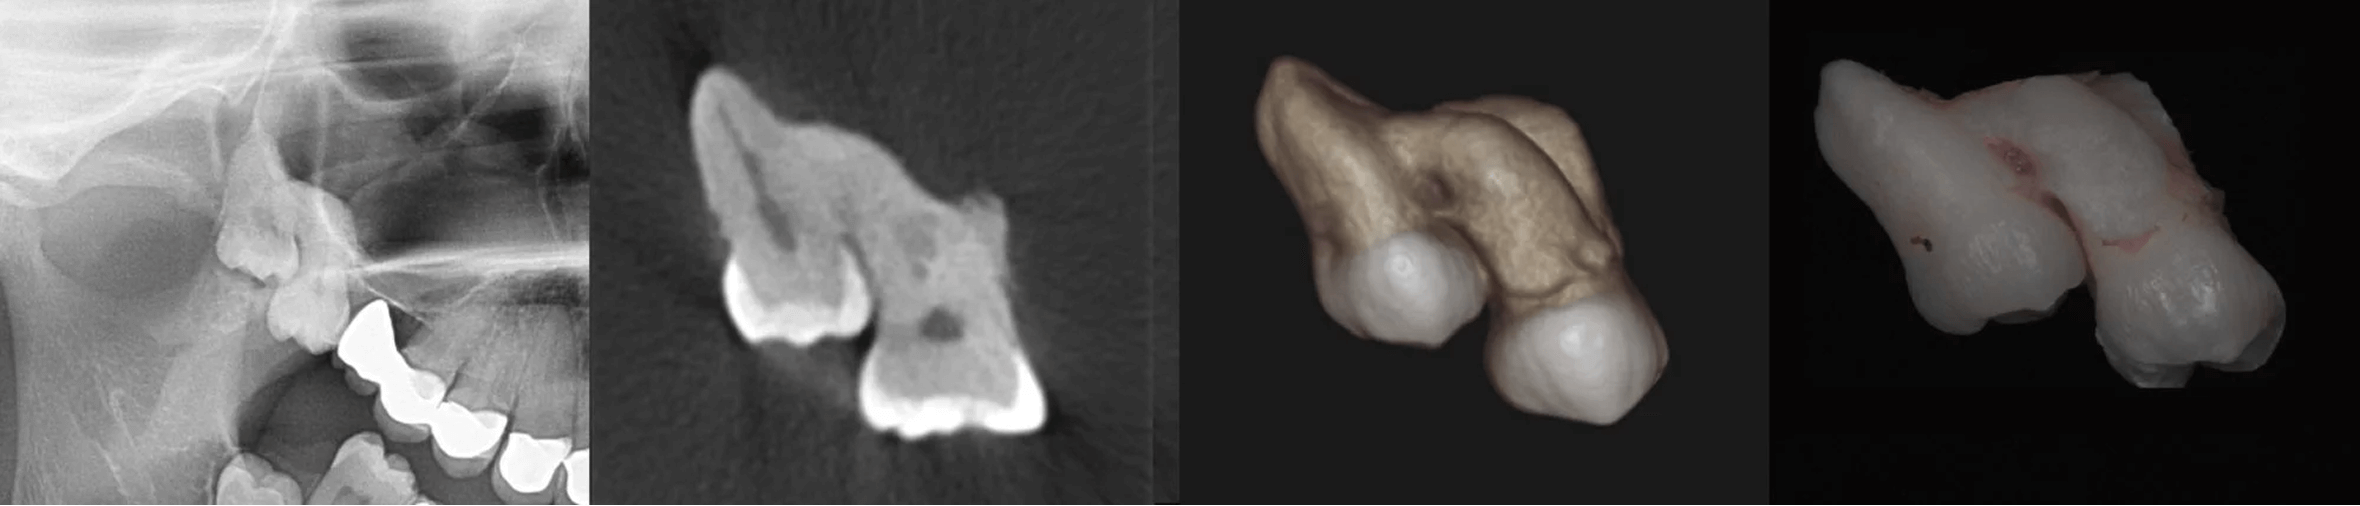

Trzecie trzonowce (ósemki) górne i dolne, potocznie nazywane zębami mądrości, powinno się usuwać, gdy zaistnieją ku temu wskazania. Kwalifikujemy je do ekstrakcji, gdy nie rokują wyrżnięcia w prawidłowej pozycji, są przyczyną powtarzających się stanów zapalnych, powodują problemy ze zgryzem, na zdjęciach rentgenowskich widoczne są wokół ich koron kieszenie kostne lub są przyczyną rozległych torbieli zawiązkowych.

Przy łatwym dostępie do zębów ósmych usunięcie zazwyczaj kończy się ekstrakcją prostą.W sytuacji zęba zatrzymanego lekarz decyduje o jego chirurgicznym usunięciu. Po wyjęciu zęba oczyszcza zębodół i zabezpiecza szwami ranę.Przy prostej i chirurgicznej ekstrakcji pacjent jest znieczulony miejscowo i nie odczuwa bólu. W sytuacji kwalifikacji pacjenta do ekstrakcji wszystkich zatrzymanych zębów mądrości podczas jednego zabiegu, ze względu na jego złożoność i czas wykonania procedury można wykonać zabieg w znieczuleniu ogólnym.